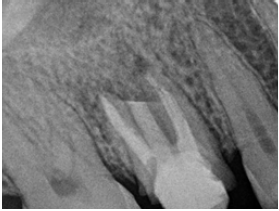

A healthy 34-year-old female presented to Endodontic Department at School of Dentistry, University of Buenos Aires with discomfort on the right palate area. Clinical examination revealed a full provisional crown on tooth #3 and sinus tract on the molar area of the palate (Figure 1). Radiographic examination and CBCT axial view showed previous nonsurgical root canal treatment and fiber post placed in the palatal root. A gutta-percha point size 20 .02 following the sinus tract was placed (Figure 2 & 3) Palatal root-end surgery was discussed and agreed with patient.

Figure 2: Pre op. radiograph with a gutta-percha point size 20 .02 following the sinus tract.

Apical root resection was performed with Piezomed handpiece and B6 instrument (W&H Dentalwerk Bürmoos GmbH, Bürmoos, Austria). The cutting level was then evaluated with post op. digital radiograph (Figure 5).

Figure 5: Post op. radiograph.